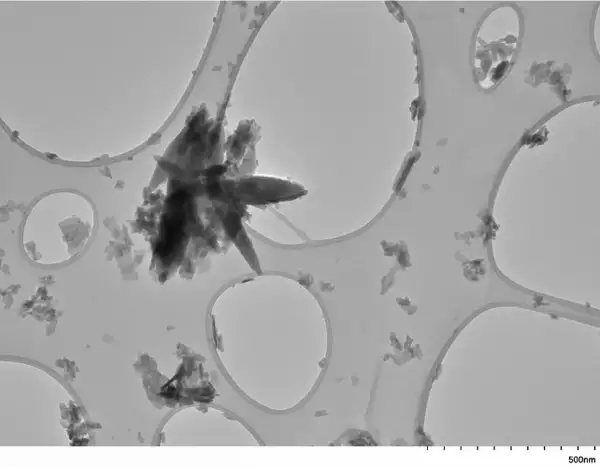

Мікроскопічні частинки пластику, або “мікропластик”, знайдені практично всюди на планеті. Ці мініатюрні забруднювачі потрапляють до людського тіла. Вони циркулюють у кровотоці та накопичуються в органах. Вчені зафіксували їх присутність у легенях, печінці та навіть мозку.

Відстеження мікропластику в організмі залишається складним завданням. Команда використовувала термічну деградацію для ідентифікації пластику. Зразки нагрівали до температури понад 538°C.